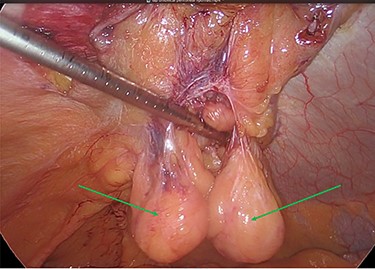

The decision was taken intraoperatively to leave the lipomas in situ as the hernia neck had been repaired, and it was thought that they could no longer cause any issue with pain or possible hernial reincarceration (Fig. 7).

Mesh reperitonealization and parietal peritoneal lipomas in situ (green arrows).